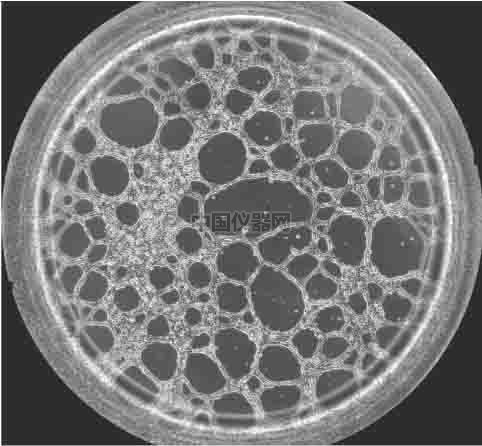

圖一 血管生成鏡檢圖 一.實驗材料和實驗方法 1.實驗材料

4、采集圖像并統計結果 可以按照細胞的生長速度定時采集圖像,并且對其成管長度,覆蓋面積,成環數,結點數進行測量和記錄,并且對其進行統計分析。